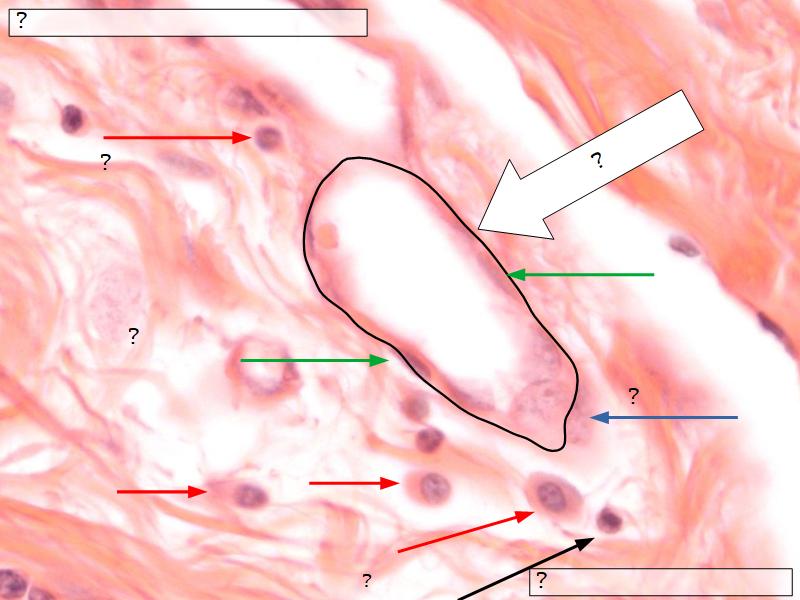

Mammary gland

Write short notes describing the structure of the mammary gland.

Resting gland

- Connective tissue dominate

- More adipose tissue

- Glandular tissue reduced

Active gland

- Terminal ducts expand

- Forms alveoli

- Connective tissue reduced

- Adipose tissue reduced

- Glandular tissue dominate

Structures

List the structures and cells found in the mammary gland.

Structures

- Lactiferous sinuses

- Stratified squamous near opening on skin

- Stratified cuboidal other parts

- Lactiferous ducts

- Stratified cuboidal

- Myoepithelial cells

- Underlie lactiferous ducts in most areas

- Basal lamina

- Separate epithelial components from stroma

Active gland

- Much larger than resting phase

- Terminal ducts proliferate to form alveoli

- Alveoli

- Surrounded by incomplete myoepithelial cells

Alveolar cells

- Apocrine secretion

- Active state

- Resting state